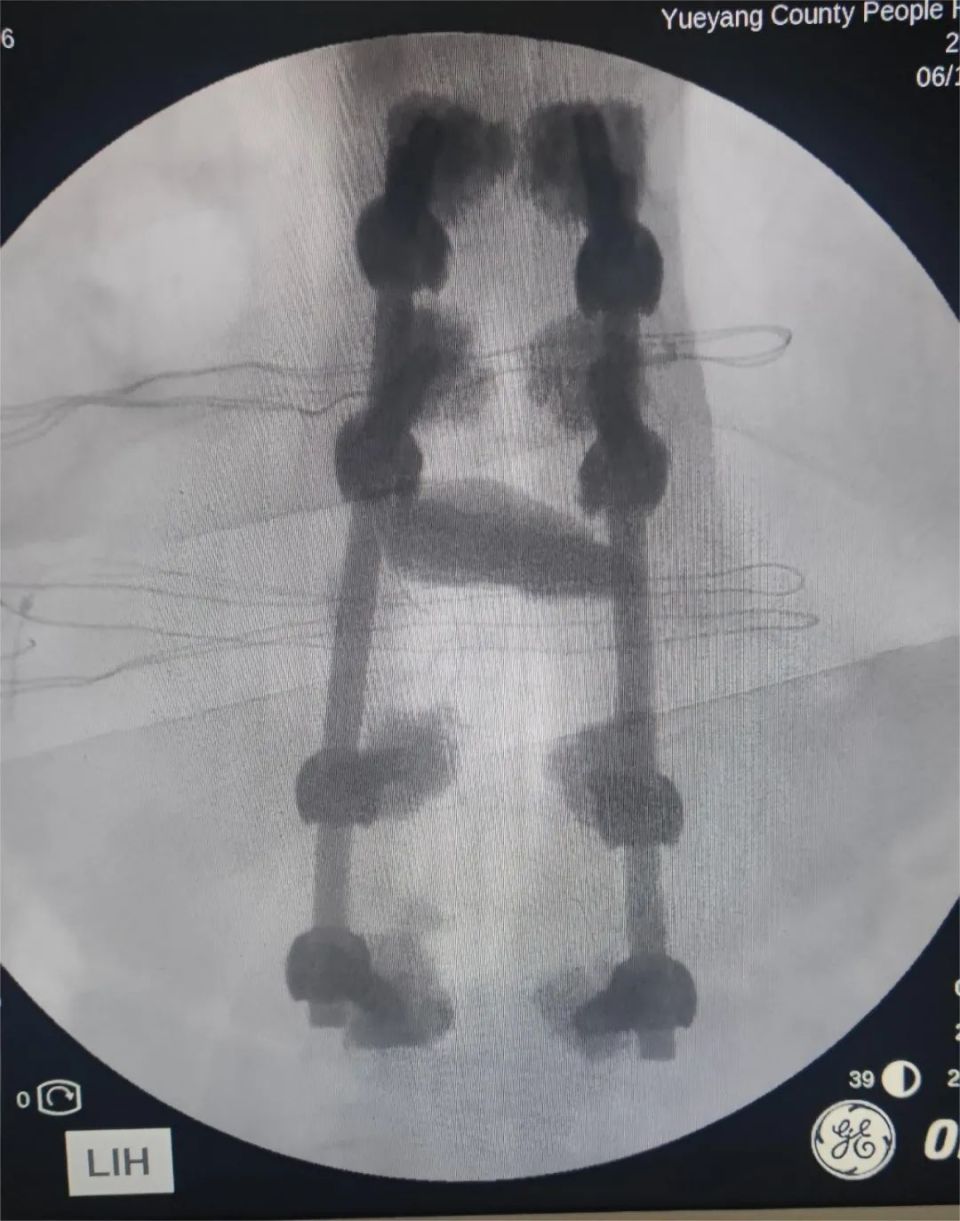

经神经脊柱外科多次术前讨论,在岳阳市人民医院钟炯彪主任医师指导下,决定为患者实施经皮骨水泥螺钉+伤椎椎体成形术。

术中、术后影像(8钉2棒)

椎弓根螺钉置入螺钉周围骨水泥强化(增强螺钉把持力及稳定性)钉棒系统进行伤椎复位并固定伤椎内骨水泥强化。

该手术可有效缓解腰背疼痛、改善伤椎 Cobb 角与椎体前缘高度,术后恢复快,强于PVP及PKP术式,是一种更安全、更有效的术式。